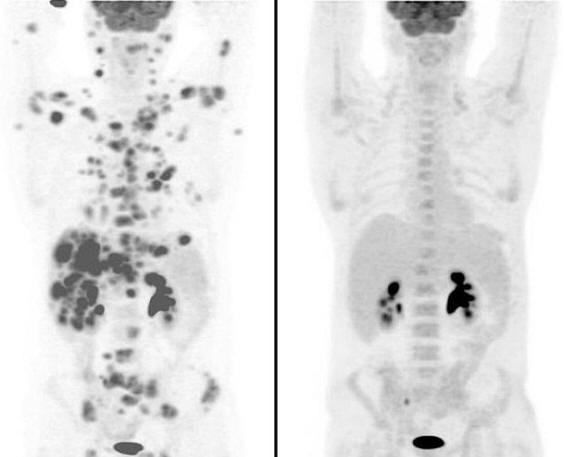

Rák ritka és agresszív formájában szenvedő személy Nagy-Britannia Jan Brooks, akinek a testét kb rosszindulatú daganatok, az orvosok legoptimistább előrejelzései szerint csak néhány hét maradt. Az orvosok elismerték szinte az összes kezelési lehetőséget kipróbálta. Ennek ellenére csalódó előrejelzések szerint a 47 éves Brooks jelenleg van teljes remisszióban van, miután az első olyan személy, aki kipróbált egy új rákellenes gyógyszert. tovább a képek megmutatják, hogy a rák mennyire terjedt az ember testében. A második vizsgálat azonban csak néhány hét alatt elkészült az új gyógyszer bevétele után hihetetlen javulást mutatott. Képek a kezelés előtt és után

Fotók nyílt forrásból Minden daganat megsemmisült. A képekben csak a sötét foltok láthatóak a vesék és a hólyag normál működése. klinikai A manchesteri krisztikus kórházban végzett vizsgálat kiderült Ha sikeres volt a gyógyszer, úgy döntöttek, hogy kipróbálják más betegeket is. Most olyan betegek, akiknél a Hodgkin-lymphoma ugyanolyan ritka formája van – egy olyan rákfajta, amely a nyirokcsomókat is érinti megkapja a gyógyszert. “Nem hiszem, hogy ma itt lennék ennek a gyógyszernek. Orvosom annyira izgatott volt, amikor meglátta eredmények, amelyek azonnal megmutatták számomra. 70 éves volt daganatok és mind eltűntek “- mondta Brooks a Mail Online interjújában, Autószerelő a Bolton-tól. Az embernek a rák ritka formája volt, amely anaplasztikus nagysejtes non-Hodgkin-nek hívják lymphoma. Betegségét 2001-ben diagnosztizálták és eleinte jól reagált a kezelésre, de 2008-ban – visszatért. Egy ember őssejt-transzplantáción megy keresztül, de rákos visszatért, kezdve gyorsan elterjedni. Tekintettel erre az orvosok azt hitték, hogy csak néhány hete van életben, Brooks úgy döntött, hogy részt vesz a klinikai vizsgálatokban. A beteg állapota javulni kezdett az indítást követő első 24 órán belül a gyógyszer és az Európa legnagyobb rákközpont orvosai sújtottak, miután megtekintette a szkennelési eredményeket. Csak 12 hetes kezelés után onkológusok azt találták, hogy a teste teljesen megszabadult a daganatoktól. Szerintük Brooks jelenleg teljes állapotban van elengedés.